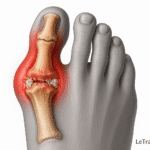

Tendinopathies et inflammations : péroniers, Achille, tibial postérieur

- Les tendons sont les structures les plus souvent responsables des douleurs remontantes.

- Tendinite d’Achille : douleur postérieure irradiant vers le mollet.

- Tendinite des péroniers latéraux : douleur externe ascendante.

- Tendinite du tibial postérieur : douleur interne, parfois confondue avec une douleur veineuse.

Souvent présente en cas de tendinopathie chronique ou d’arthrose sous-talienne débutante.

- Précieuse pour évaluer les tendons péroniers, le tendon d’Achille ou le tibial postérieur.